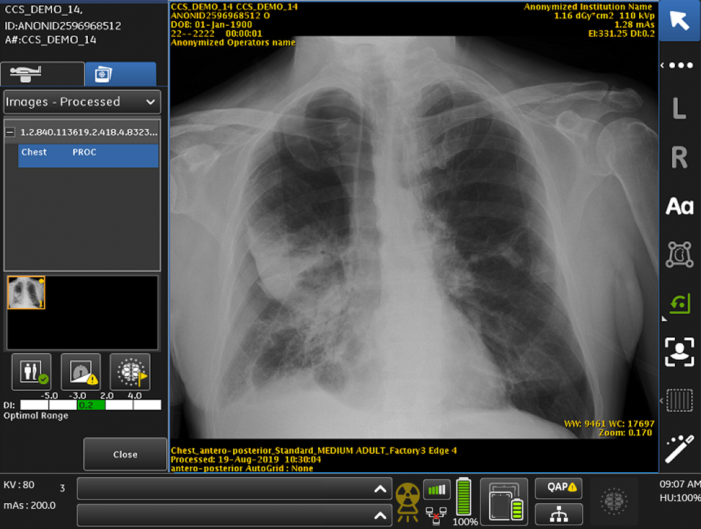

Pneumothorax X Ray Findings - Pneumothorax Ppt - It's as easy as abc).. Chest xray in pneumothorax, pneumothorax imaging. X ray findings of pneumothorax include a discrete shadowed line beyond which no lung markings are present, as shown by the arrows. Learn vocabulary, terms and more with flashcards, games and other study tools. Findings on lung auscultation vary depending on the extent of the pneumothorax. What should you look for on your x ray to assess it?

In most cases of pneumothorax related to other causes, findings consistent with the … conclusion: A film is under penetrated if you cannot see the spine behind the heart. It's as easy as abc). Ipsilateral hemithorax may be more lucent. X ray findings of pneumothorax include a discrete shadowed line beyond which no lung markings are present, as shown by the arrows.

X ray findings of pneumothorax include a discrete shadowed line beyond which no lung markings are present, as shown by the arrows. Along with symptoms such as breathlessness, establishing the size of a pneumothorax helps to determine management. What should you look for on your x ray to assess it? Radiology body radiology tension pneumothorax: Respiratory findings may include the following Most patients with surgically treated pneumothorax have emphysema or an isolated bulla. Pneumothorax black and white : Reduction in lung markings in the apices (erect). Large hemothoraces can obscure underlying pulmonary contusions. This leads to a loss of negative pressure between the two unstable patients with tension pneumothorax require immediate needle decompression. It is considered a simple pneumothorax when there isn't any mediastinal shift to. In most cases of pneumothorax related to other causes, findings consistent with the … conclusion: The sensitivity of plain films varies from study to study, from well below 50% to a high of about 80%.